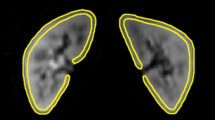

To determine whether a mono-, bi- or tri-exponential model best fits the intravoxel incoherent motion (IVIM) diffusion-weighted imaging (DWI) signal of normal livers.

The pilot and validation studies were conducted in 38 and 36 patients with normal livers, respectively. The DWI sequence was performed using single-shot echoplanar imaging with 11 (pilot study) and 16 (validation study) b values. In each study, data from all patients were used to model the IVIM signal of normal liver.

The tri-exponential model provided a better fit than both the bi- and mono-exponential models. The tri-exponential IVIM model determined three diffusion compartments: a slow (D1 = 1.35 ± 0.03 × 10-3 mm2/s; f1 = 72.7 ± 0.9 %), a fast (D2 = 26.50 ± 2.49 × 10-3 mm2/s; f2 = 13.7 ± 0.6 %) and a very fast (D3 = 404.00 ± 43.7 × 10-3 mm2/s; f3 = 13.5 ± 0.8 %) diffusion compartment [results from the validation study]. The very fast compartment contributed to the IVIM signal only for b values ≤15 s/mm2